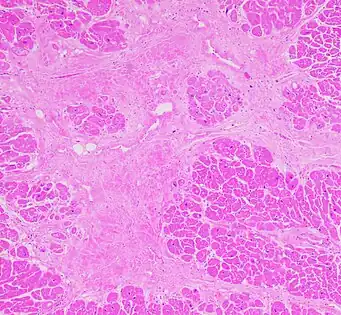

Interstitial fibrosis of chronic ischemic heart disease, H&E stain, with associated relatively well organized myocardial bundles